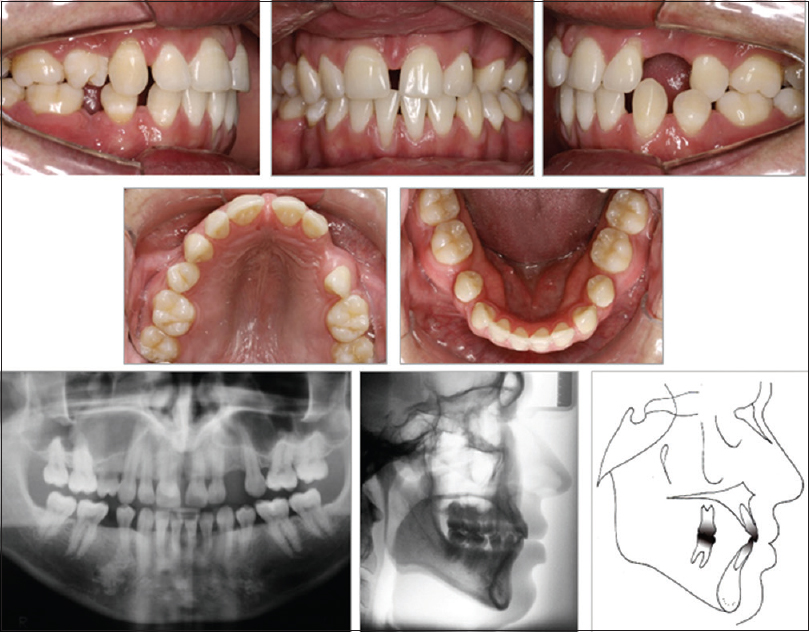

Horizontal tooth movement through atrophic edentulous alveolar ridge for bone formation

p. 106

Ivan Pedro Taffarel, Oscar Mario Antelo, Lara Karolina Guimarães, Laís Cristina Giacobbo, Orlando Motohiro Tanaka

DOI

The absence of premolars is relatively common, occurring approximately 1.5% in the maxilla, but the absence of the both premolars in the same arch is rare and usually observed in cases of oligodontia. The objective of this article is to present a clinical case with a malocclusion in the permanent dentition and an absence of both premolars in the left hemiarch, and with the canine positioned adjacent to the maxillary left first molar. The movement of the canine was slow through the alveolar ridge in the edentulous region during movement. Rectangular arches associated with stainless steel open springs alternated with elastomeric chains were used to move the canine adjacent to the lateral incisor. The retention was with a Hawley type and an acrylic tooth while waiting for implant prosthesis placement. The orthodontic movement, even to a significant extent of the maxillary canine through the atrophic alveolar bone, generated new bone, obviating the need for bone grafting. The result with the implant placement of a premolar achieved good dental and functional occlusion with improved esthetics and periodontal health, which was evident by improvements in patient self-esteem and satisfaction.